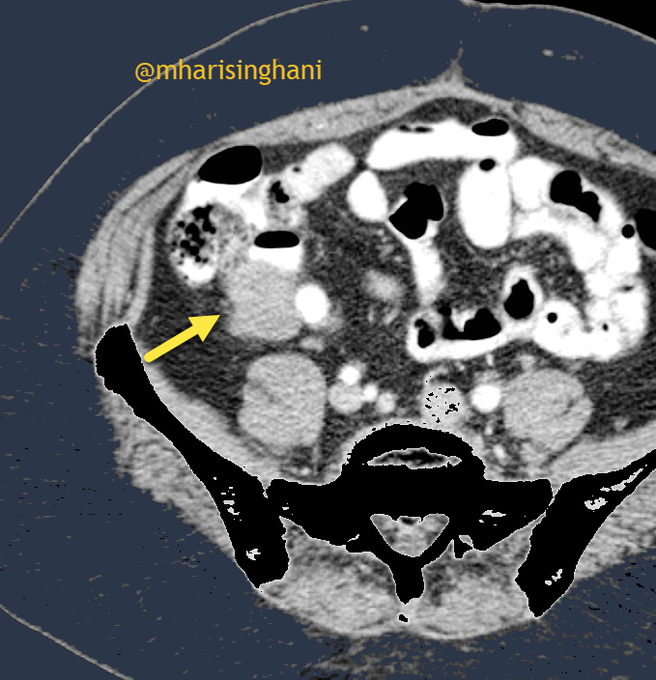

Young female patient with abdominal pain; is that a worrisome lesion arising from the wall of cecum; appendix was separately visualized and normal. was resected and was endometriosis implant on the wall of the cecum

12 60